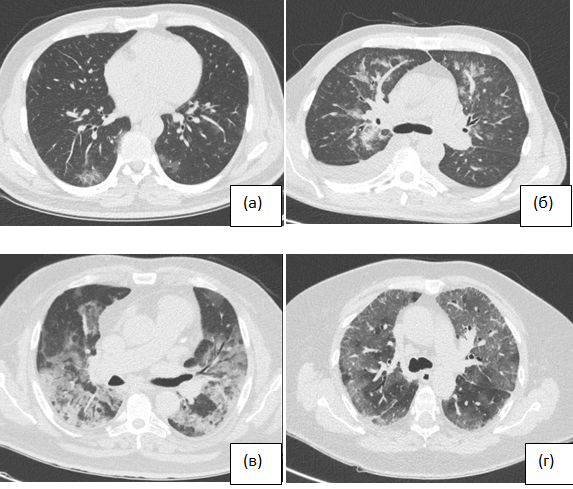

Обоснование. Вспышка коронавирусной инфекции 2019 года (COVID-19) быстро ― всего за месяц ― охватила весь мир. В диагностике этого заболевания помогает метод полимеразной цепной реакции (ПЦР), однако данный тест имеет ограничения, связанные с ложноотрицательными результатами, а также сроками выполнения. С учётом повышенного распространения инфекции компьютерная томография (КТ) органов грудной клетки (ОГК) может стать одной из основных методик в арсенале клинициста для раннего выявления COVID-19 у впервые обратившихся за медицинской помощью пациентов.

Цель ― сравнение частоты внебольничных пневмоний и их характеристик по данным КТ в многопрофильной больнице Москвы до начала и во время эпидемии COVID-19 и изучение возможностей их своевременного выявления и дифференциального диагноза.

Материалы и методы. Проведён ретроспективный анализ результатов КТ грудной клетки пациентов Городской клинической больницы имени И.В. Давыдовского (Москва) за период с 1 по 17 апреля 2020 года. В исследование включены все пациенты с диагнозом вирусной пневмонии по заключению КТ. Всем пациентам с подозрением на вирусную пневмонию выполняли тестирование ПЦР. В качестве группы сравнения ретроспективно проанализированы данные КТ грудных клеток пациентов с подозрением на пневмонию за аналогичный промежуток 2019 г.

Результаты. С 1 по 17 апреля 2020 г. по данным КТ ОГК пневмония диагностирована в 140 случаях, из которых 65 (46,4%) описаны как вирусные, в сравнении с тем же периодом 2019 г. ― 7 (10,3%) диагнозов вирусной пневмонии: наблюдается значимое увеличение частоты вирусных пневмоний (5,723; р <0,01). Результаты ПЦР-теста у пациентов с вирусной пневмонией по данным КТ: положительный ― у 34 (52,3%), отрицательный ― у 22 (33,8%), у 9 (13,9%) больных тест не проводился. При сравнении частоты обнаружения на КТ паттернов вирусной пневмонии у пациентов за одинаковый промежуток времени в 2019 и 2020 гг. не было обнаружено никаких достоверных различий. Вероятность COVID-19 по КТ-картине ОГК: средняя ― 13,8%, высокая ― 75,4%. Тяжесть вирусной пневмонии по данным КТ ОГК: лёгкая ― 38,5%, среднетяжёлая ― 46,2%, тяжёлая ― 12,3%, крайне тяжёлая ― 3,1%.

Заключение. КТ-диагностика COVID-19, в том числе при ложноотрицательных результатах ПЦР-тестов, позволяет вовремя изолировать пациента с подозрением на COVID-19, своевременно приступить к лечению и предотвратить дальнейшее распространение вирусной инфекции в условиях пандемии. Однако ввиду неспецифичности выявляемых изменений возможности КТ для идентификации поражения лёгких конкретными вирусными агентами ограничены.